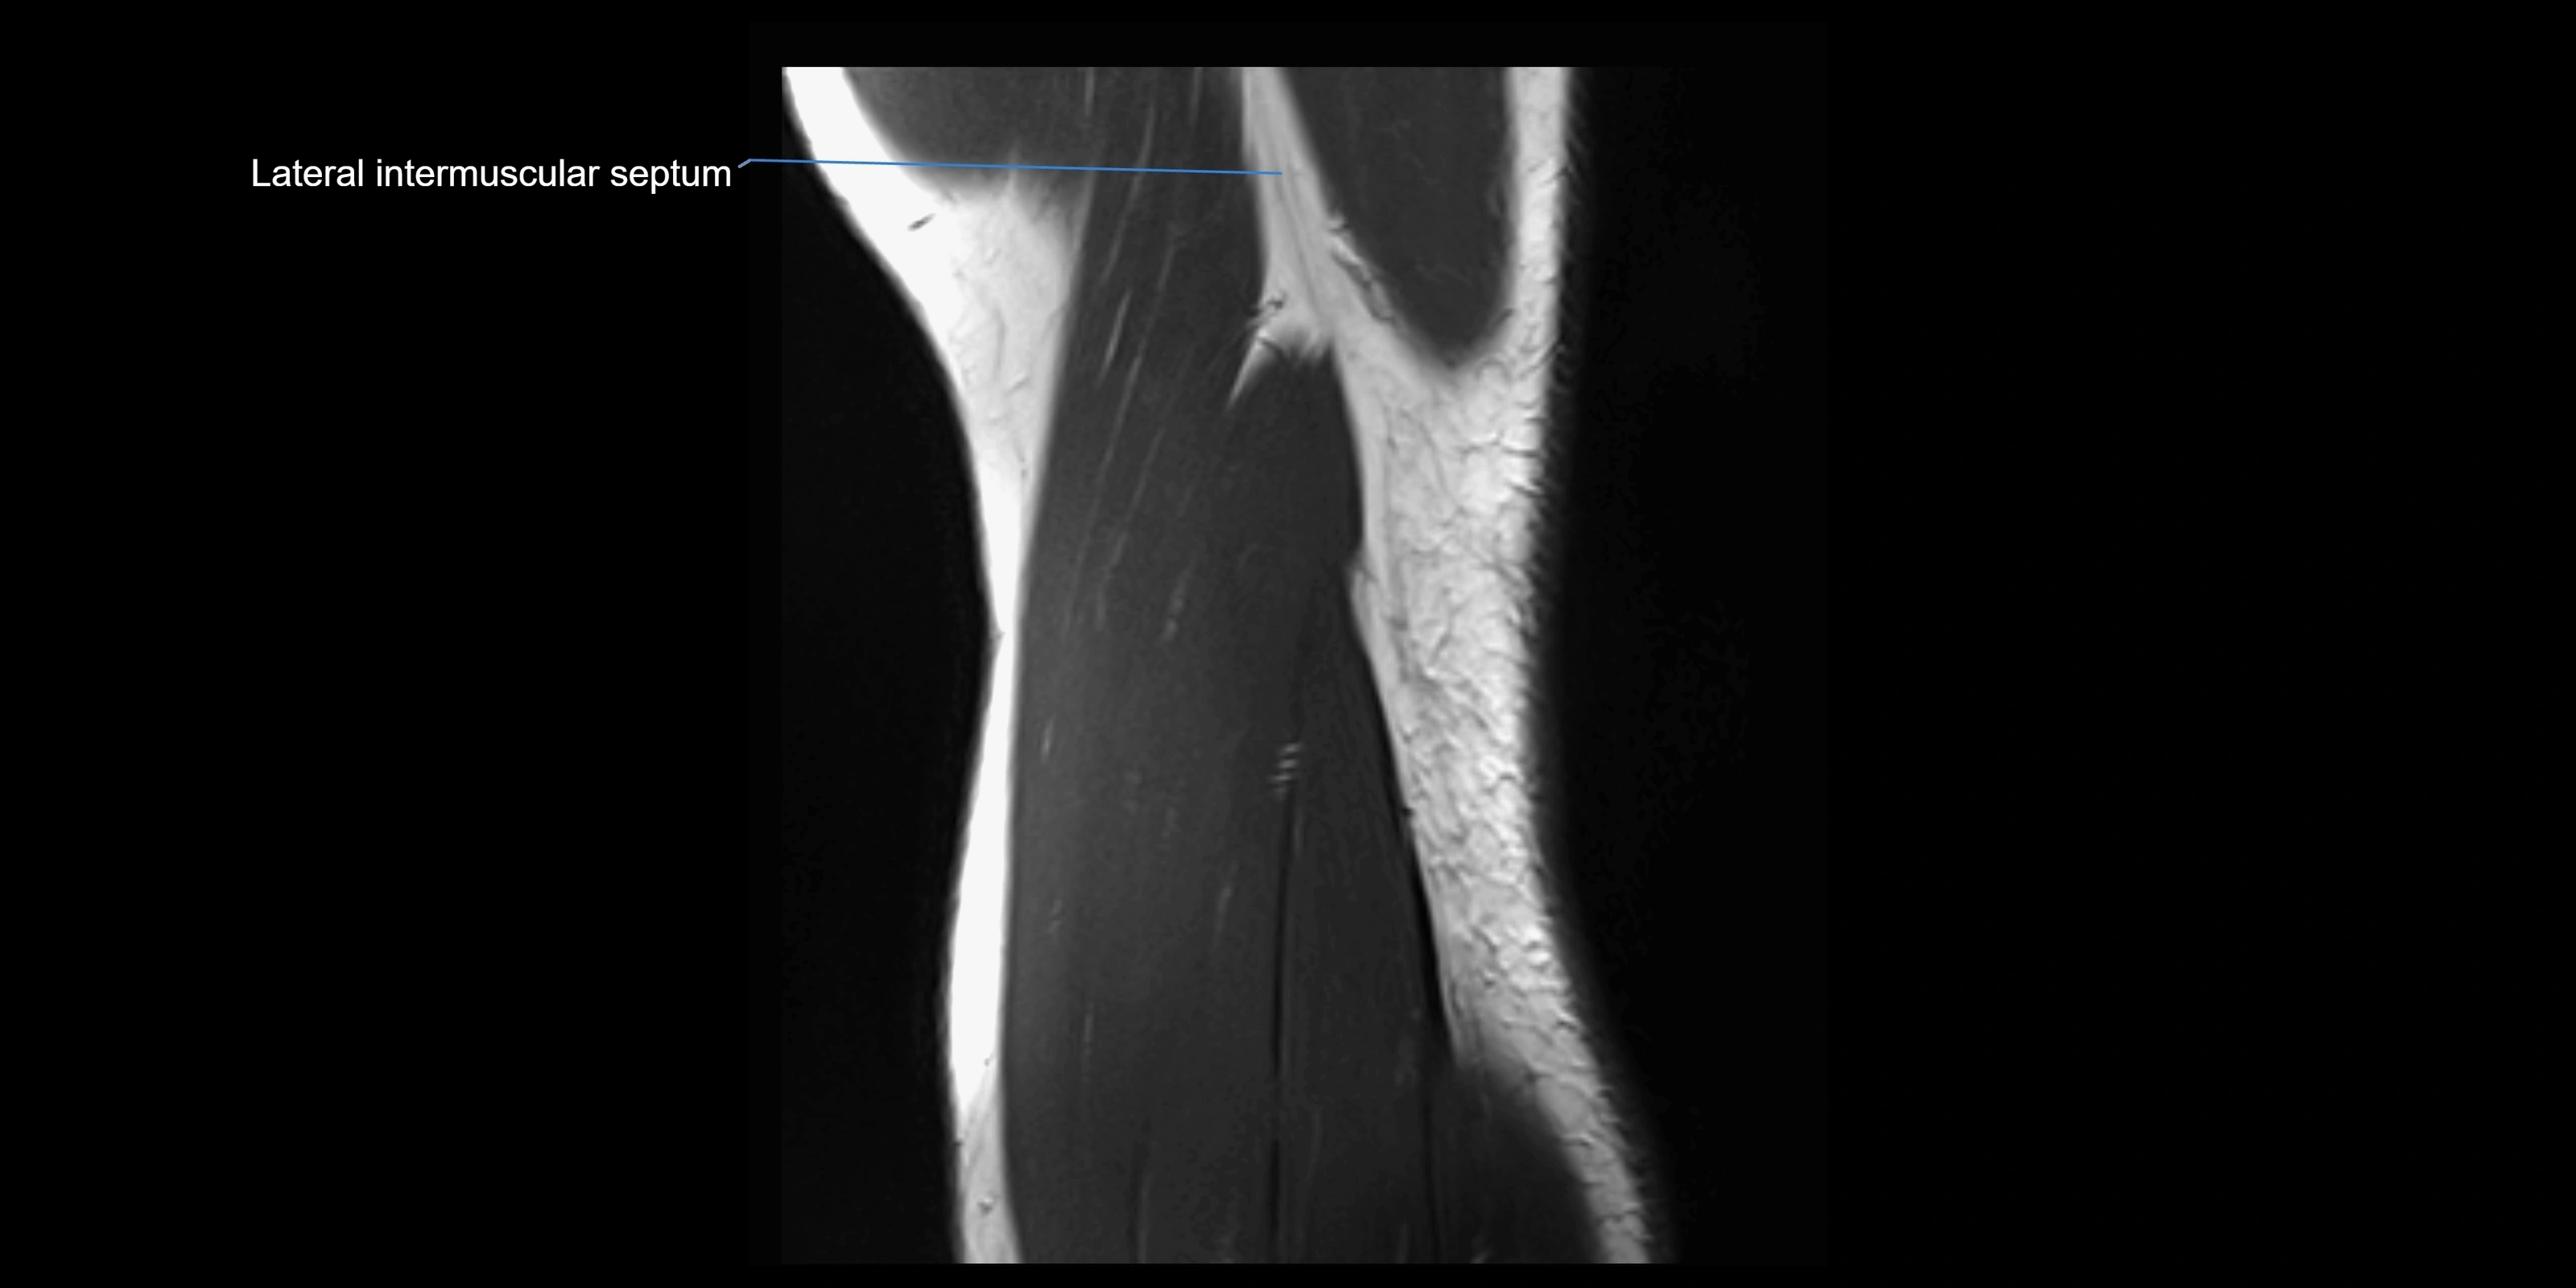

MRI images

image